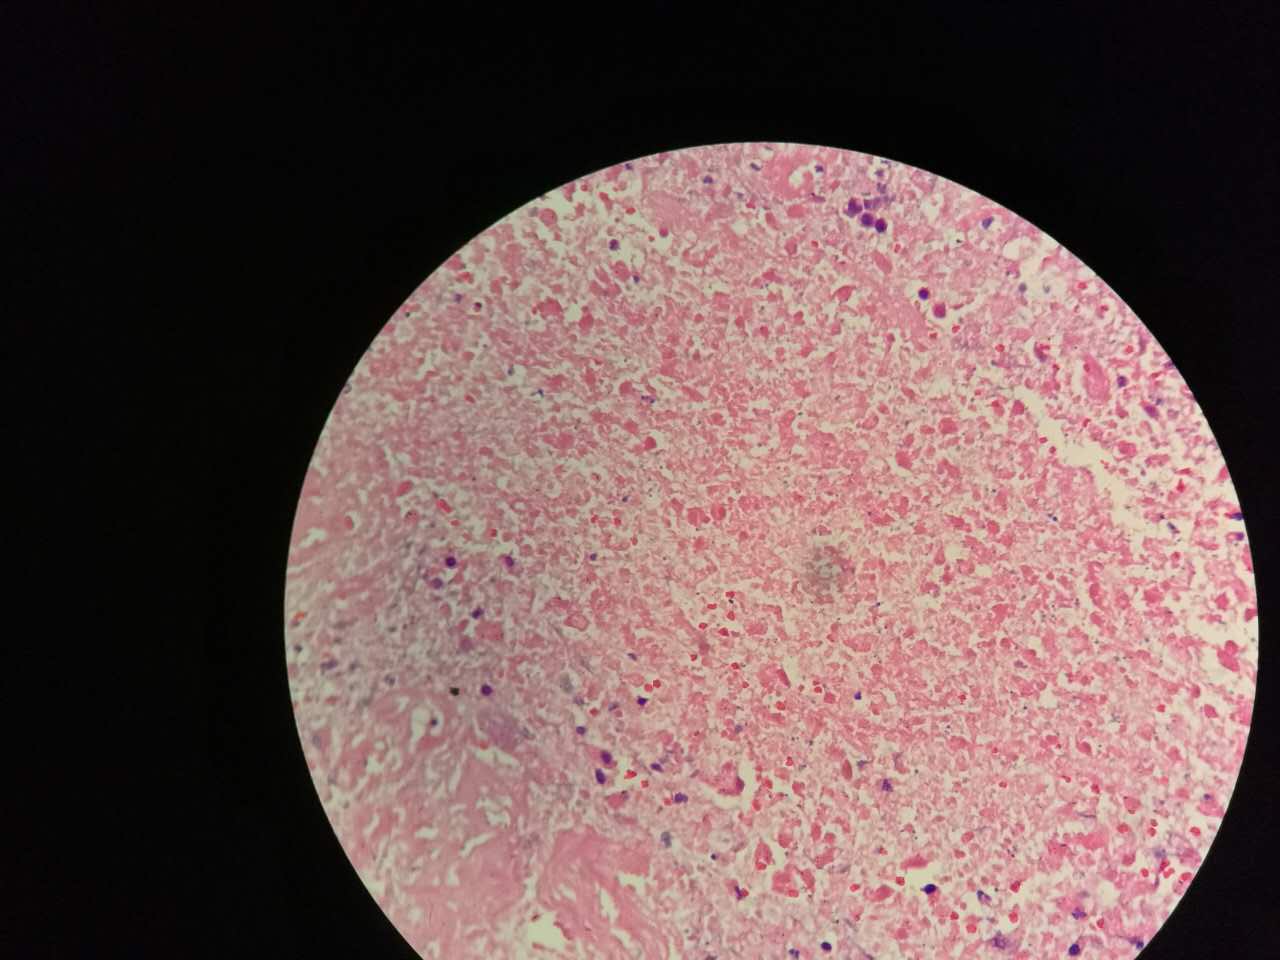

这一幅的上方都是黏液湖

下方是正常肺泡

细胞内白颜色区是粘液,细胞外洋流样的也是粘液(湖)

黏液湖里可以飘着一些细胞,吞噬细胞及肿瘤细胞。

肿瘤细胞飘出去可以种植于肺泡上。